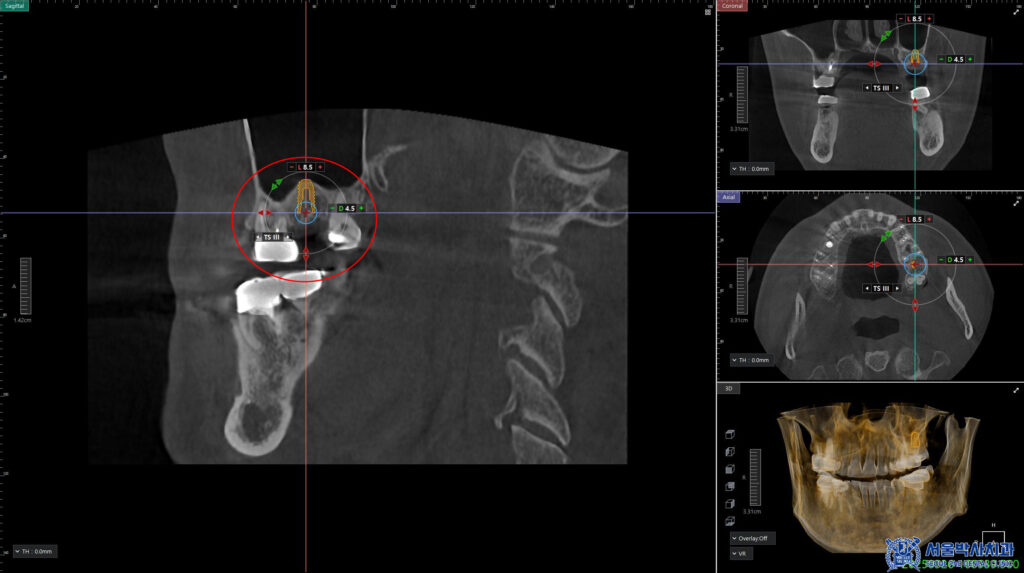

CT를 촬영하여 식립 위치를 확인하며

뼈의 높이와 두께, 그리고 상악동과의 거리를

정밀하게 확인을 하였습니다.

먼저 왼쪽 위 임플란트를 식립하면서

상악동거상술도 같이 진행하였습니다.

상악동거상술이란 위쪽 어금니 부위에

임플란트를 식립할 공간을 확보하기 위해

상악동을 들어올리고

뼈이식을 진행하는 수술입니다.

이는 임플란트가 안정적으로

자리잡을 수 있도록 하고

예후가 좋아집니다.